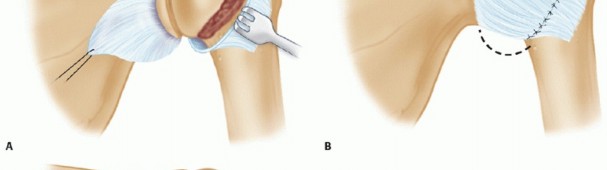

A longitudinal incision in the posterior axillary fold is made beginning at a point 2 cm medial to the posterolateral corner of the acromion and extending distally, following the posterior axillary line (TECH FIG 3).

Third, the infraspinatus may be completely detached, leaving a 2-cm remnant of the tendon still attached for later repair (TECH FIG 4). It is tagged and carefully released from the underlying thin capsule. - Capsulotomy

A vertical capsulotomy is made on the humeral side with the arm in neutral rotation (TECH FIG 5A).

A small amount of capsule, 3 to 4 mm, can be left on its humeral attachment to aid in repair of the capsular flaps laterally during the shift.

Care is taken to protect the axillary nerve inferiorly from retractors as it is traversing from anterior to posterior to exit in the quadrangular space inferiorly.

TECH FIG 5 • A. The infraspinatus is elevated as a single layer, exposing the underlying posterior capsule. A vertical capsulotomy is then made based on the humeral side from the 12 o'clock to the 6 o'clock position. B. Traction stitches are then placed as the medial capsule is divided horizontally, between the sutures, toward but not through the glenoid labrum.

With the vertical capsulotomy completed, two traction stitches are placed at the midposition and the capsule is horizontally divided, between the stitches, toward the middle of the glenoid rim, stopping 1 to 2 mm from the posterior glenoid labrum (TECH FIG 5B).

Posterior Inferior Capsular Shift

The posterior glenoid labrum is inspected and if there is a small detachment, it is repaired before

completing the capsular shift procedure.

The inferior flap of the capsule is carefully mobilized past the 6 o'clock position, inferiorly on the humerus.

This step is critical as an inadequate release of the inferior capsule will prevent correction of the posteroinferior capsular redundancy and volume.

The nonarticular sulcus, medial to the capsular remnant left behind, is then decorticated with a high-speed burr to facilitate healing (TECH FIG 6A).

The inferior capsular flap is brought superiorly and slightly laterally with the arm held in 40 to 45 degrees of abduction and 15 to 20 degrees of external rotation.

This inferior flap is sutured in place with multiple figure-eight nonabsorbable sutures.

If the capsular remnant stump is of poor quality, suture anchors are used for repair. In a similar fashion, the superior capsular flap is shifted inferiorly down over the inferior flap and sutured (TECH FIG 6B,C*).

The horizontal portion of the T capsulorrhaphy is then closed and reinforced with nonabsorbable sutures.

The degree of closure of this horizontal portion can further tighten the posterior capsule if desired.

TECH FIG 6 • A. With the capsular flaps fully developed, the metaphyseal area between the capsular insertion and the articular surface is decorticated using a motorized burr. B,C. The arm is then brought into slight extension and the inferior capsular flap is first shifted superiorly with the arm positioned in about 45 degrees of abduction. The superior capsular flap is subsequently shifted inferiorly.*